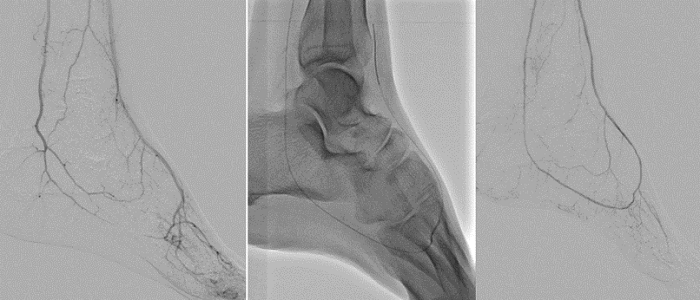

(왼쪽) 협착을 보이는 투석환자의 종아리 동맥이 (중간) 혈관개통술 시행으로 (오른쪽) 치료된 후의 모습.

이런 종아리동맥의 협착과 폐쇄는 동맥 내로 가느다란 관을 넣어 이를 개통하는 혈관개통술로 치료할 수 있습니다. 위 치료 영상사진을 보면 (왼쪽 사진) 막히고 좁아진 종아리 동맥들이, (중간 사진) 풍선관(노란색 화살표)을 이용한 혈관개통술 후, (오른쪽 사진) 현저히 개선된 것을 알 수 있습니다.

(왼쪽) 투석환자의 막혀있는 발 동맥이 (중간) 혈관개통술 시행 후 (오른쪽) 혈류가 개선된 모습.

위 사진은 (왼쪽 사진) 투석환자의 발바닥 동맥이 막혀 있는 사진입니다. (중간 사진) 발등과 발바닥 동맥을 연결하는 개통술 후에 (오른쪽 사진) 발등과 발바닥, 그리고 발가락의 혈류가 현저히 개선된 모습을 확인할 수 있습니다.